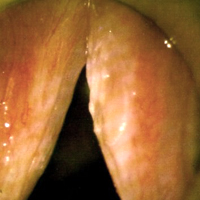

라인케씨 부종

성대의 겉껍질과 고유층의 바깥층을 함께 일컫는 라인케씨 공간에 부종이 발생하는 질환으로 음성을 남용해서 성대가 손상된 것입니다.

음성의 과다사용과 흡연이 주 원인이며, 갑상선기능저하증, 인후두역류, 환경오염, 만성 부비동염으로 인한 후비루의 자극이 영향을 줄 수 있습니다. 이런 원인들에 의해 라인케씨 공간 내에 림프액이나 정맥혈이 고임으로써 나타난 것이며 점차 크기가 커지면서 영구적인 병변이 됩니다. 매우 커지게 되면 후두내시경검사상 성대가 마치 물이 든 풍선 혹은 물주머니처럼 보이게 됩니다.

지속적인 쉰목소리가 주 증상이며 대부분의 환자는 낮은 톤의 목소리로 변합니다.

치료는 일차적으로 금연, 음성 안정과 음성치료가 필요하며, 원인질환이 있는 경우 그 치료를 우선 시행해야 합니다. 보존적 치료만으로 완전히 소실될 가능성은 희박하며 치료반응이 미약한 경우 후두미세수술로 치료하게 됩니다. 수술 후에도 흡연과 음성남용이 계속될 경우에는 재발률이 높으므로 환자에 대한 교육이 대단히 중요합니다.